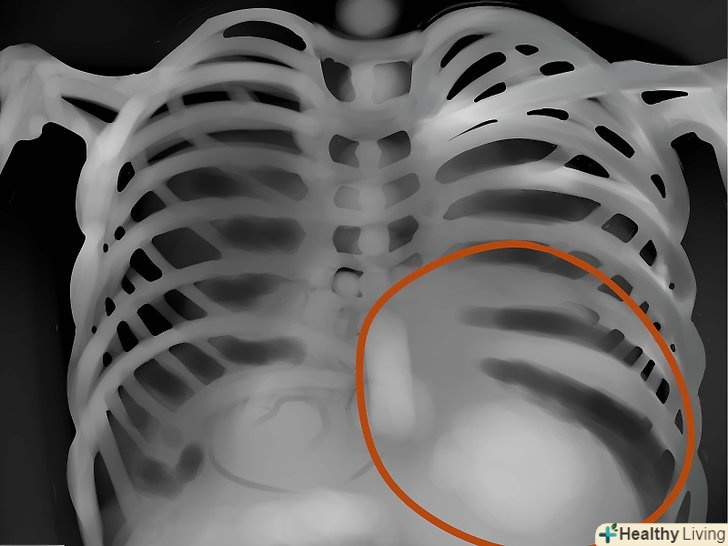

Області легенів.оцініть симетричність, васкулярність, наявність сторонніх мас, вузликів, інфільтрату, рідини і т.д. якщо в легкому слиз, кров, гній, пухлина або щось ще-то ця область буде яскравіше, а інтерстиціальні позначки - менш помітні.